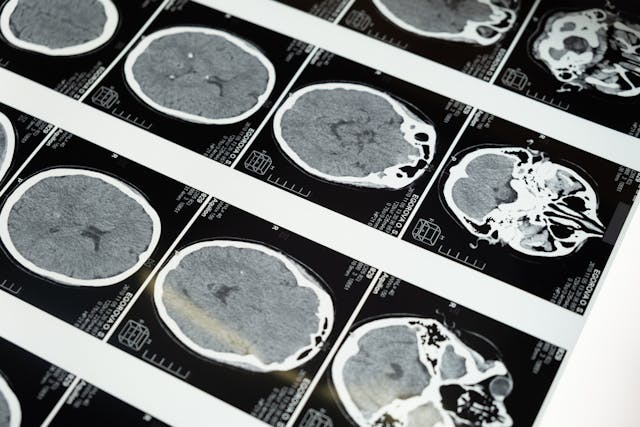

I februar 1988 råka ein livstrugande aneurisme som feilaktig hadde blitt klassifisert som ein samanklemt nerve, Joe Biden, som no er 81 år gammal. Legar fann ei bekymringsverdig forvrenging av ein blodarterie etter at pasienten måtte ta opp til ti smertestillande per dag for å få ei viss smertelindring. Det blodkaret hadde mest sannsynleg ført til døden om det hadde sprukke.

For å behandle sjukdommen og hindre dei potensielt dødelege effektane, undergjekk Biden naudoperasjon. Ei blodåre som har blitt vridd, ser ofte ut som ein bul eller ei boble, og blir kalla ein aneurisme. Aneurismar har potensial til å sprekke etter å ha blitt fylt med blod. Aneurismar er dødelege i rundt 50% av tilfelle der dei sprekk. To tredjedelar av overlevande vil oppleve langsiktig svekking av hjernen.

Biden vart råka av ein lungeembolisme under sin rekonvalesens. Dette kan vere ein potensielt dødeleg sjukdom, som er karakterisert av ei plutseleg tilstopping av arteriane som forsyner lungene med blod. Etter den fyrste aneurismen vart oppdaga i februar 1988, vart ein andre oppdaga i mai same år, noko som gjorde at Biden nok ein gong måtte opererast.

Aneurismar kan utvikle seg gradvis hjå ein pasient, og kan vere arveleg. Med tanke på denne 81-åringen si historie med aneurismar, kan dette vere endå ein grunn til å bekymre seg for den nøye overvaka helsa til Biden.